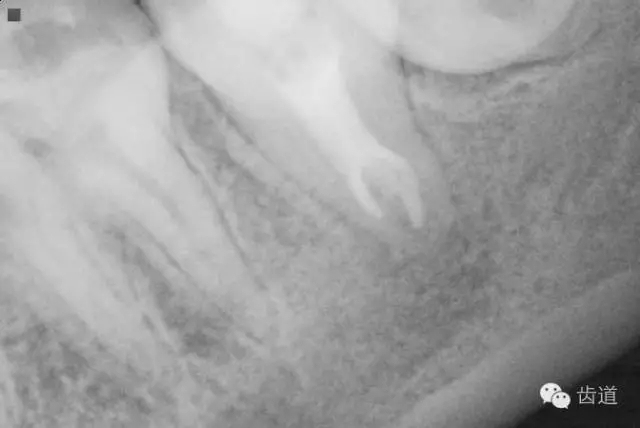

2. 術(shù)前X片

可見37根管影像清晰,根中上三分之二粗大,根尖三分一分為近遠(yuǎn)中兩根管,形態(tài)均呈弧形,根尖周膜連續(xù)性中斷,根尖周透射影明顯